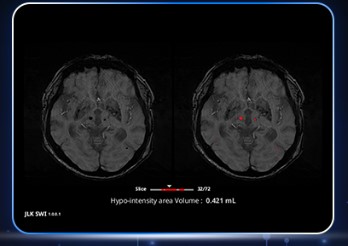

SWI는 뇌 내부의 미세한 출혈 흔적 등을 저신호 영역으로 나타내 아주 작은 병변도 확인할 수 있는 강점이 있다. 그러나 3차원 영상으로서 슬라이스 두께는 얇고 해상도는 높은데다가, 한번 촬영에서 생성되는 이미지 개수도 다른 영상에 비해 월등히 많아 판독에 어려움이 있었다. 의료진들은 지금까지 이를 일일히 세고 기록하는 작업을 통해 병변을 확인할 수밖에 없어 피로도와 부담이 컸던 게 현실이다.

제이엘케이의 SWI 솔루션은 이러한 어려움을 해소하고 보다 빠르고 정확하게 병변을 검출·계산할 수 있도록 지원함으로써 임상적 효용성을 크게 높인 게 특징이다. 의료진들의 피로도와 부담을 개선해 진단 프로세스를 단축시키고, 나아가 환자들의 치료까지 이르는 시간을 대폭 단축할 수 있을 것으로 전망된다.